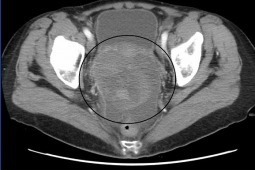

Lekarze z Kliniki Onkologii i Chirurgii Onkologicznej Dzieci i Młodzieży w Instytucie Matki i...